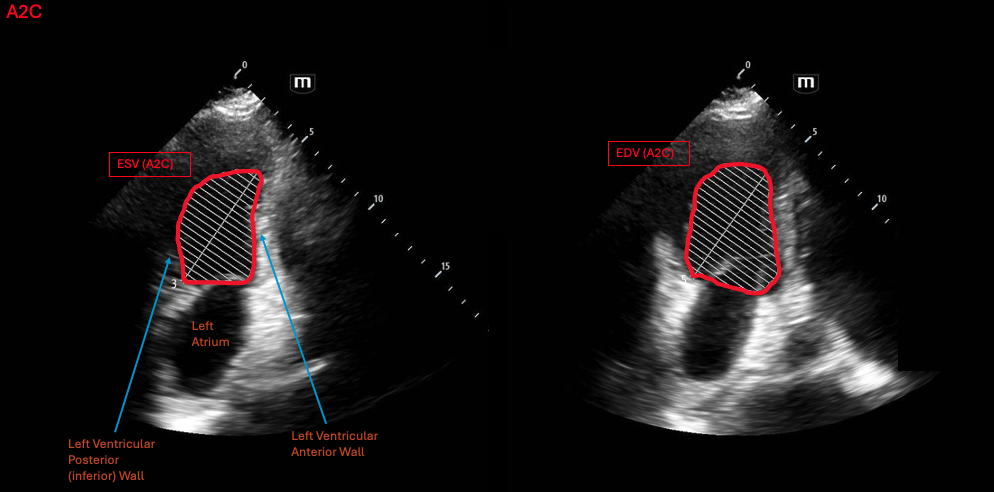

How to do

The biplane method requires two views, one in the A4C for the mediolateral measurements and another in the apical 2 chamber view (A2C) for the posteroanterior measurements of the heart. Both these planes also measure length of the LV in the base-apex axis.

Similar to FAC, the LV border is traced during end-diastole and end-systole. These tracings are taken in the A4C and A2C, resulting in a total of 4 tracings to make the final measurement. The ultrasound will take these tracings, convert them to volume measurements and utilize this to estimate an ejection fraction.

Normal values

Since the biplane method calculates volumes, the normal parameters are the normal values for LVEF. The normal range for LVEF is 55-69% and severely reduced LVEF is <30%.